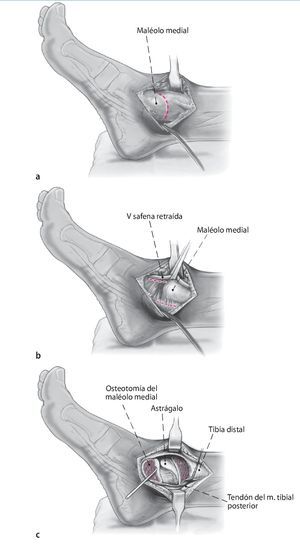

Fig. 2 La incisión medial se lleva a cabo hasta el periostio (a). El daño a la vena safena mayor se evita mediante su retracción anterior. En el lado anteromedial, se reseca parcialmente la cápsula anterior (b). El retináculo extensor y los tejidos blandos se pueden mover como una capa para exponer la sección anteromedial de la articulación del tobillo. Se realiza incisión posterior del retináculo sobre el tendón tibial posterior para permitir la colocación protectora de un separador de Hohmann (b). La osteotomía del maléolo medial se realiza con sierra oscilante y se reseca la porción distal (c).